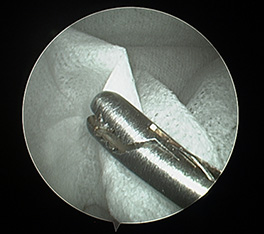

関節鏡を用いて内視鏡下で関節内を確認できる関節鏡検査が可能です。

レントゲン検査や整形外科学的検査だけでは、診断が困難な場合、関節鏡検査が非常に有用です。

これまでの前十字靭帯断裂の手術では膝関節を大きく切開していましたが、関節鏡検査では膝関節の2か所に数mmの切開を加えるのみなので低侵襲です。

また関節鏡検査では前十字靭帯断裂に伴う半月板損傷の診断率が有意に高いとの報告があります。

| 関節鏡は大きく拡大できるので、小切開で診断・手術が可能です。 |